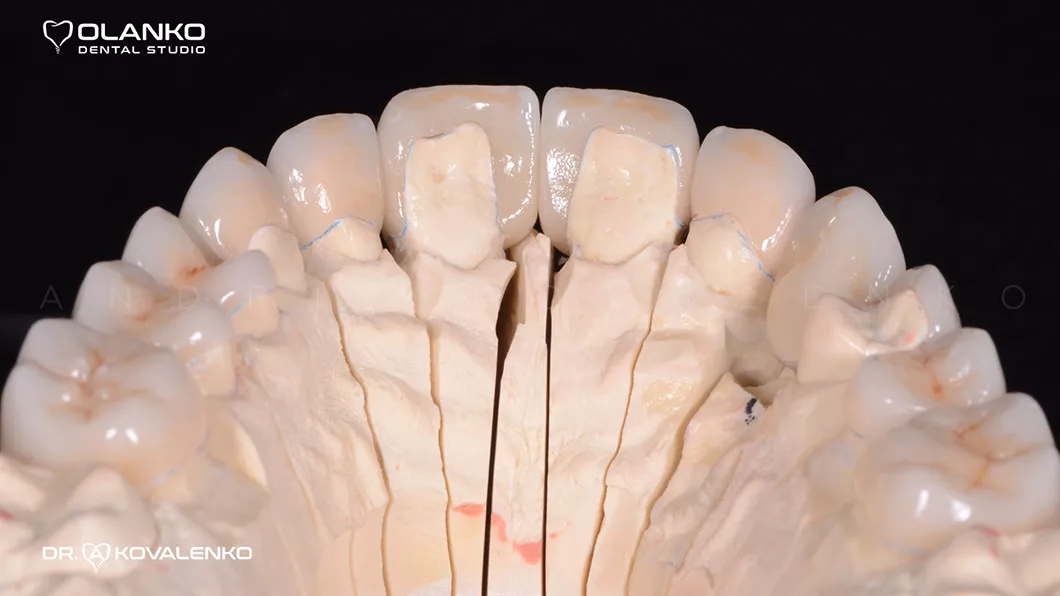

Клинический случай 3 протезирование

Диагностика: эстетический анализ, создание проекта новой улыбки DSD (цифровой дизайн улыбки).

Протезирование:12 керамических реставраций (коронки,виниры на зубах и имплантате) на верхней челюсти.